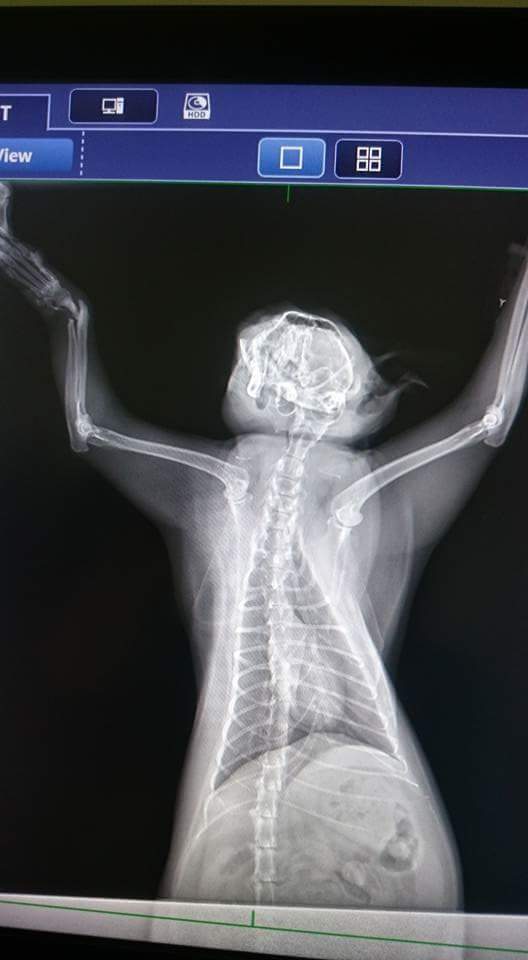

主題: 被補獸夾 夾傷的小花 申請者姓名: 許芸瑄 花色: 申請日期: 2017-02-16 20:27:48 申請者部落格: 申請者臉書網址: rebecca9907@hotmail.com 所在縣市/合作醫院: 台北市/澄諾動物醫院 治療費用: 10300元 需求人數: 24人 已結案 (2022-05-13 15:15:05) 報名人員: 帕尼尼(已付款)、薇薇安(已付款)、minmi(已付款)、Paula Li(已付款)、Kitty Chen、邱小比(已付款)、王小盈(已付款)、Vicky Tung(已付款)、Yi-Ling Yao x2(已付款)、米粒(已付款)、陳珍妮 x2(已付款)、RCS x2(已付款)、野薑花(已付款)、Diamond(已付款)、Pei(已付款)、詩瑤(已付款)、Isabel Liu(已付款)、葉直育(已付款)、Mico(已付款)、陳昱先 x3(已付款)、 候補人員: 動物病情說明: 餵養時發現小花前腳無法落地走路不穩。當下就先誘補帶到醫院做檢查。經過醫生抽血拍x光整個療程下來。小花的腳可以維持現狀不用截肢。但是必需先結紮因為小花剛發情完。 動物近況說明: 小花很棒喔出院後恢復的很好。胃口很好。是隻肥胖胖的小花貓。小花的醫藥費還需要大家的幫忙。小花謝謝哥哥姐姐們。。